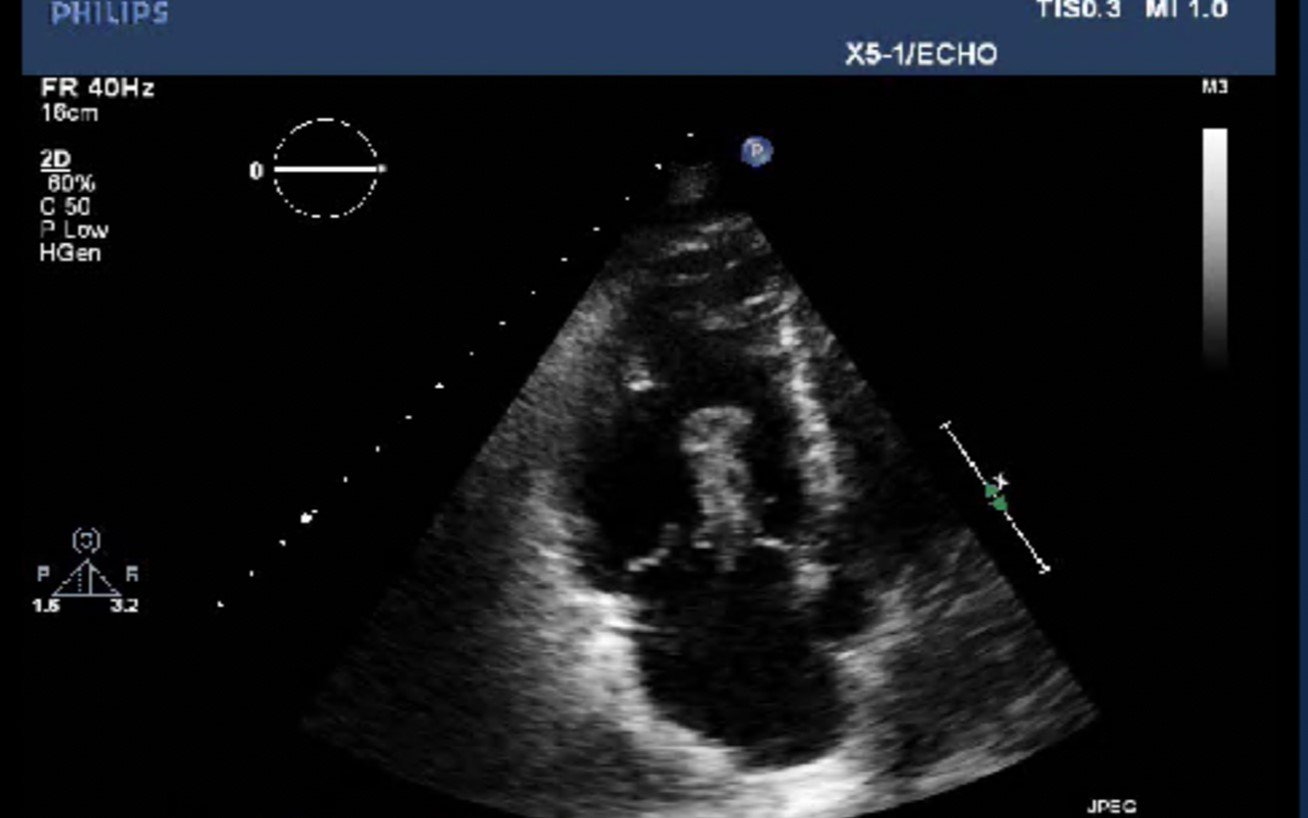

Bedside echocardiogram was performed, which revealed a free-floating thrombus in the right atrium on the sub-xiphoid view as seen in the video. The right atrium is denoted by the blue circle, in which a hyperechoic mobile mass can be seen. This finding was confirmed by an official echocardiogram which shows the thrombus in the right atrium extending through the tricuspid valve, as shown in the second image denoted by the red arrow. Significant right heart strain was also found, with severe pulmonary hypertension and intraventricular septal flattening.